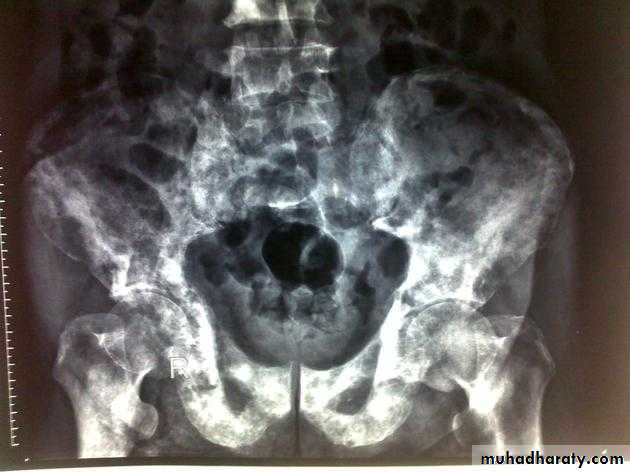

PROSTATIC Enlargement

Common cause of lower urinary obstruction . Either Benign prostatic hyperplasia or Carcinoma .Benign Hyperplasia :-

Plain film:-

* Enlargement of bladder shadow due to residual urine.

*Prostatic calculi or calcification .

• IVU ( cystogram stage )

• * Elevated bladder base .• *Lower ureter elevated and curved (fish hook ).

• * Back pressure to both kidney & ureters .

• * Thick trabeculated bladder wall and diverticula formation .

• * Large size prostate produce filling defect like appearance .

• * Post-voiding residual volume .

•

Produce similar changes except:

* Plain film shows evidence of metastasis to the bone especially in the pelvis .* The prostatic urethra shows irregular narrowing and stretching .

* US can distinguish between BPH & Ca.